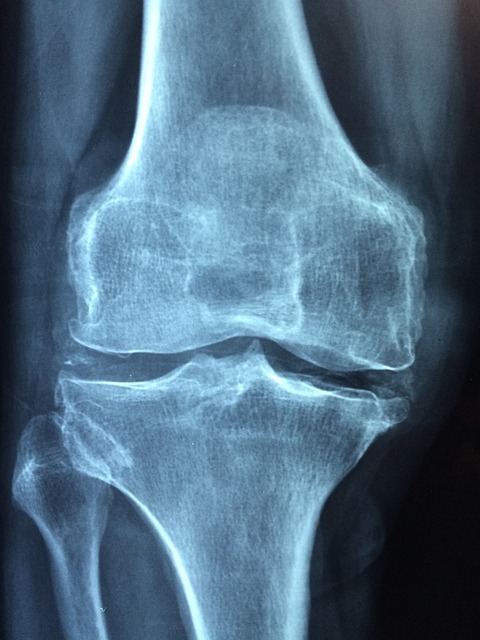

골다공증은 전 세계 수백만 명의 사람들, 특히 노인과 폐경기 여성에게 영향을 미칩니다. 뼈가 약해져서 깨지기 쉽고 골절되기 쉬운 상태를 말합니다. 골다공증은 초기에는 눈에 띄는 증상이 나타나지 않지만 방치할 경우 심각한 합병증을 유발할 수 있고 삶의 질을 저하시킬 수 있습니다. 이 종합 가이드에서는 골다공증의 증상, 치료법, 예방 조치를 자세히 살펴보고 뼈 건강에 관심이 있는 개인에게 귀중한 통찰력을 제공할 것입니다.

골절: 골다공증의 주요 증상 중 하나는 특히 척추, 고관절, 손목 및 갈비뼈에서 골절이 발생할 가능성이 증가한다는 것입니다. 이러한 골절은 경미한 외상이나 물건을 구부리거나 들어올리는 등의 일상 생활 활동에서도 발생할 수 있습니다. 골다공증이 있는 사람은 골절이 자주 발생하거나 뼈가 이전보다 더 쉽게 부러지는 것을 느낄 수 있습니다. 키 감소: 골다공증은 시간이 지남에 따라 점진적인 키 감소로 이어질 수 있습니다. 이는 척추의 압박골절로 인해 발생하며, 척추뼈가 허탈되거나 눌려 구부정한 자세를 취하고 키가 눈에 띄게 감소하게 됩니다. 골다공증 환자는 키가 감소하고 전반적인 신체 정렬이 변화하는 것을 볼 수 있습니다. 허리 통증: 만성 허리 통증, 특히 허리 통증은 특히 척추 골절과 관련된 골다공증의 흔한 증상입니다. 움직이거나 구부리거나 무거운 물건을 들어올릴 때 통증이 악화될 수 있습니다. 또한 골다공증으로 인한 척추 골절 환자는 해당 부위에 근육 경련과 경직이 발생할 수 있습니다. 뼈 약화: 골다공증이 진행됨에 따라 개인은 특히 엉덩이와 다리와 같이 체중을 지탱하는 뼈에서 뼈가 약해지거나 무거워지는 느낌을 받을 수 있습니다. 이러한 감각은 이동성과 일상 활동을 방해하여 삶의 질을 저하시키고 낙상 및 골절 위험을 증가시킬 수 있습니다. 자세 변화: 골다공증은 자세와 신체 정렬에 영향을 미쳐 일반적으로 미망인의 혹 또는 후만증이라고 하는 구부정하거나 구부정한 자세로 이어질 수 있습니다. 이러한 자세 변화는 척추 압박 골절로 인해 발생하는 경우가 많으며 불편함, 이동성 제한 및 자존감 감소에 영향을 미칠 수 있습니다.